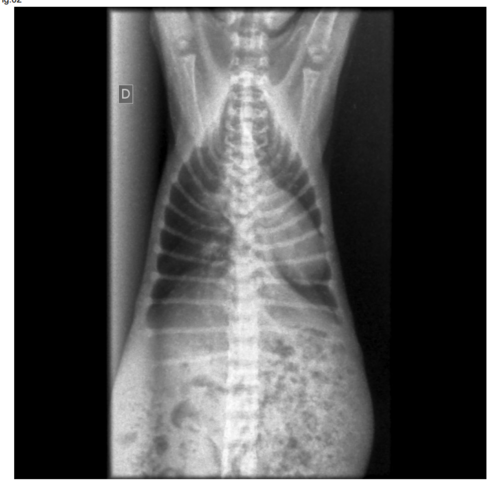

Meu nome é Bianca, estou criando essa vaquinha para poder inicialmente cobrir os exames do Jimin que tem apenas dois meses, e foi diagnosticado com uma doença rara chamada pectus excavatum. Preciso de ajuda com os custos dos exames e posteriormente com apoio para cirurgia, essa má formação congênita dificulta a respiração além do peito do animal ficar em formato de cone pressionando os órgãos do animal.Até o momento o quadro dele teve piora considerável e precisa de ajuda urgente com os exames para prosseguir com a cirurgia, qualquer valor ajuda.Segue imagens, e anexos do orçamento. Assim que tiver o custo da cirurgia compartilharei com vocês. Deus abençoe.